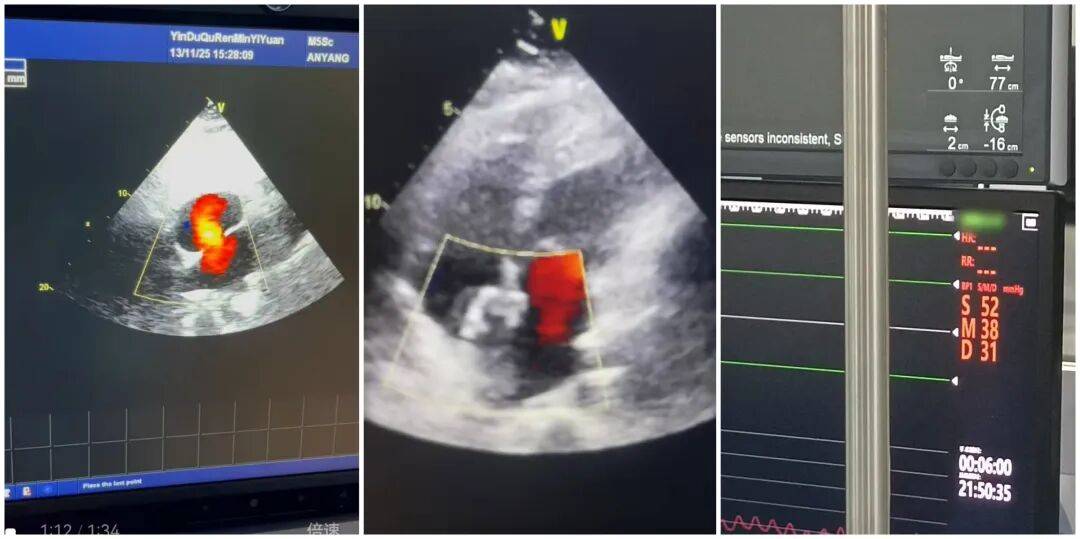

2025年11月14日,殷都区人民医院心血管内科团队顺利为39岁患者路女士完成房间隔缺损封堵术。此次手术的成功实施,不仅为患者解除了心脏健康隐患,更填补了本院在先天性心脏病介入治疗领域的一项空白,为区域内同类患者带来了就近就医的新选择。

患者入院后,心血管内科团队高度重视,立即组织多学科会诊,结合心脏超声、心电图等详细检查结果,与特邀专家共同研判病情,制定了精准的个性化手术方案。11月14日手术当天,经右心导管检查显示,路女士的肺动脉压已高达52mmHg,需尽快干预。在团队的密切配合与专家的精准指导下,手术历时36分钟顺利完成,成功对其直径约25mm的室间隔缺损进行封堵。术后即刻超声检查证实,缺损处无过隔血流,手术效果达到预期。